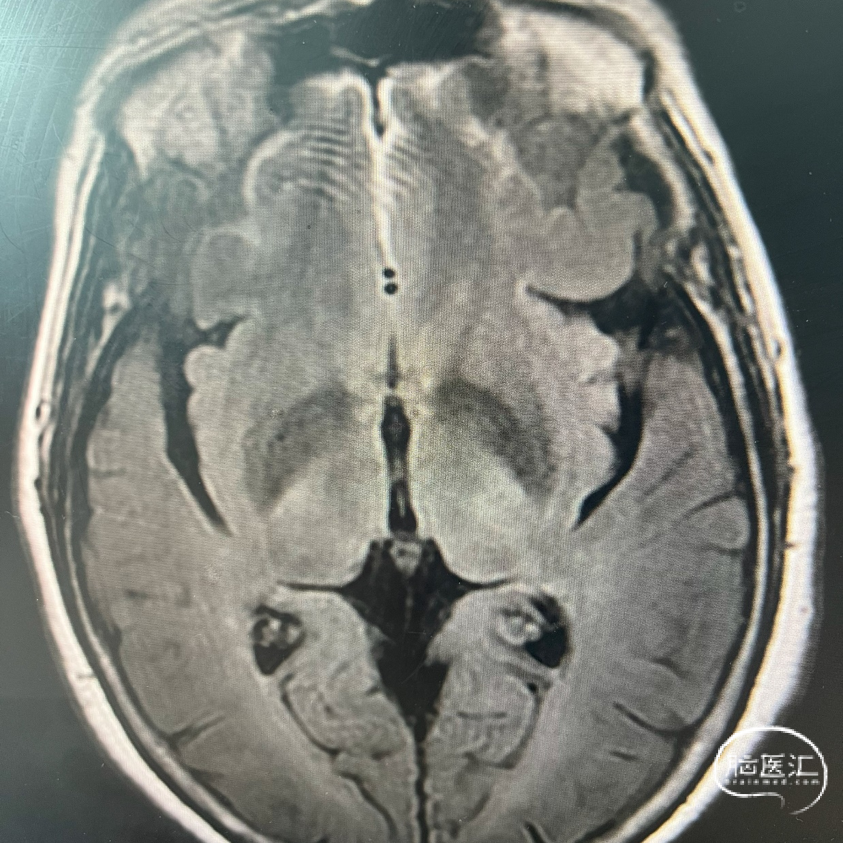

术前FLAIR

影像学表现: